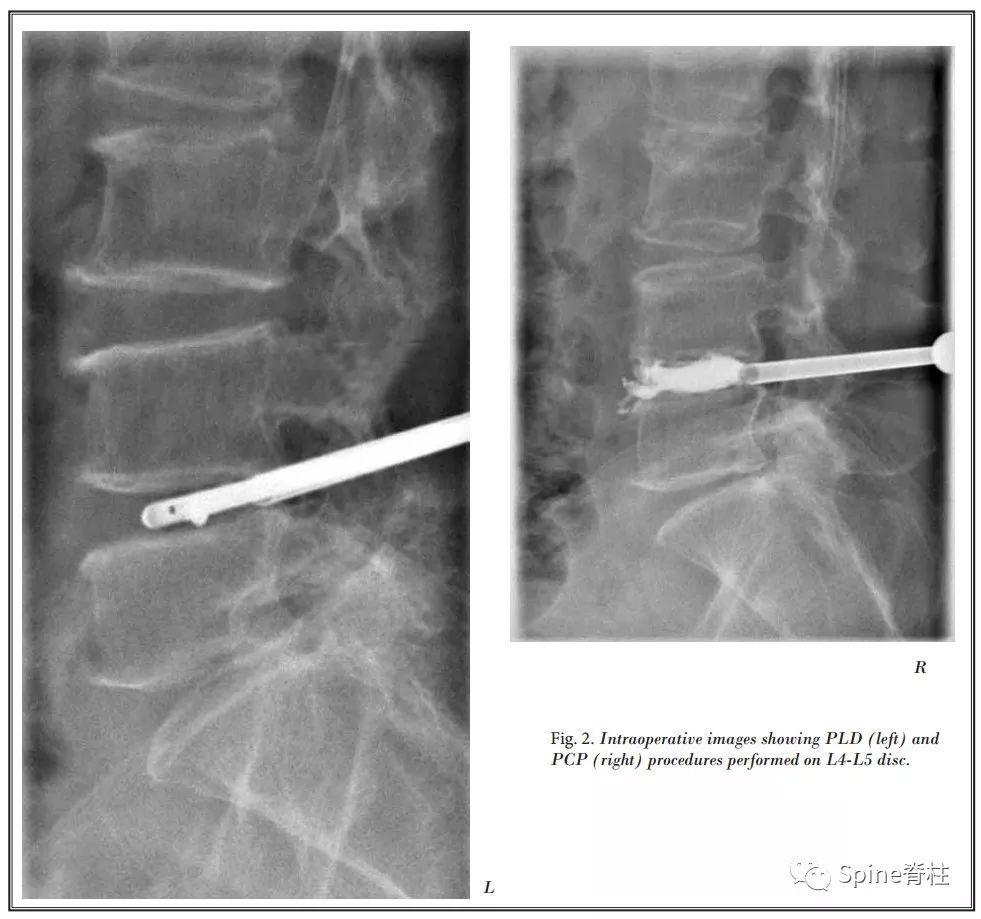

上海交通大学附属第六医院放射科Tian等将PCD与经皮腰椎间盘切除术(percutaneous lumbar discectomy,PLD)相结合治疗7例症状性腰椎间盘突出症伴终板 I型 Modic改变患者,采用局麻下后外侧入路,先进行椎间盘切除,然后进行PMMA骨水泥灌注,随访1年,VAS和ODI评分显著改善。仅1例出现骨水泥穿刺通道渗漏伴轻微腰痛,24h后缓解,未见其他明显并发症。

图: 左图为PLD(先),右图为PCD(后)

最后作者总结,PLD+PCP可作为老年腰椎间盘突出症伴I型Modic终板改变患者的可选治疗方法,对于因一般情况不佳难以耐受传统开放手术或不愿意接受开放手术的患者来说,这似乎是一个选择。此外,这是一种微创技术,可在清醒镇静下进行,并发症发生率极低,住院时间短。